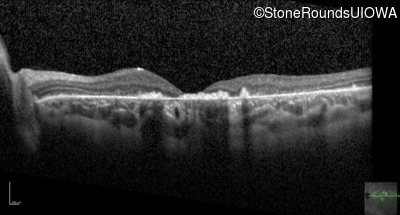

Optical Coherence Tomography - Right - 20/400 sc

Exemplar / OCT Stack

OCT Stack